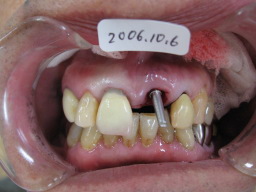

| インプラント(人工歯根)を植えた所に 仮歯(テック)を作り、手術の終わりです。 骨が固まるまで数ヶ月待ち、それから、 はずした歯(補綴物)が入ればそれを 入れます。 歯の周りにあるのは、ゴムで、血(血餅)が流れ 出ないようにしています。こうする事によって、 きれいな歯ぐきが再生されます。 |

| インプラントして1週間後の状態です。 歯ぐきの傷はほとんど治っています。 仮歯(テック)の状態で、半年程待ちます。 |